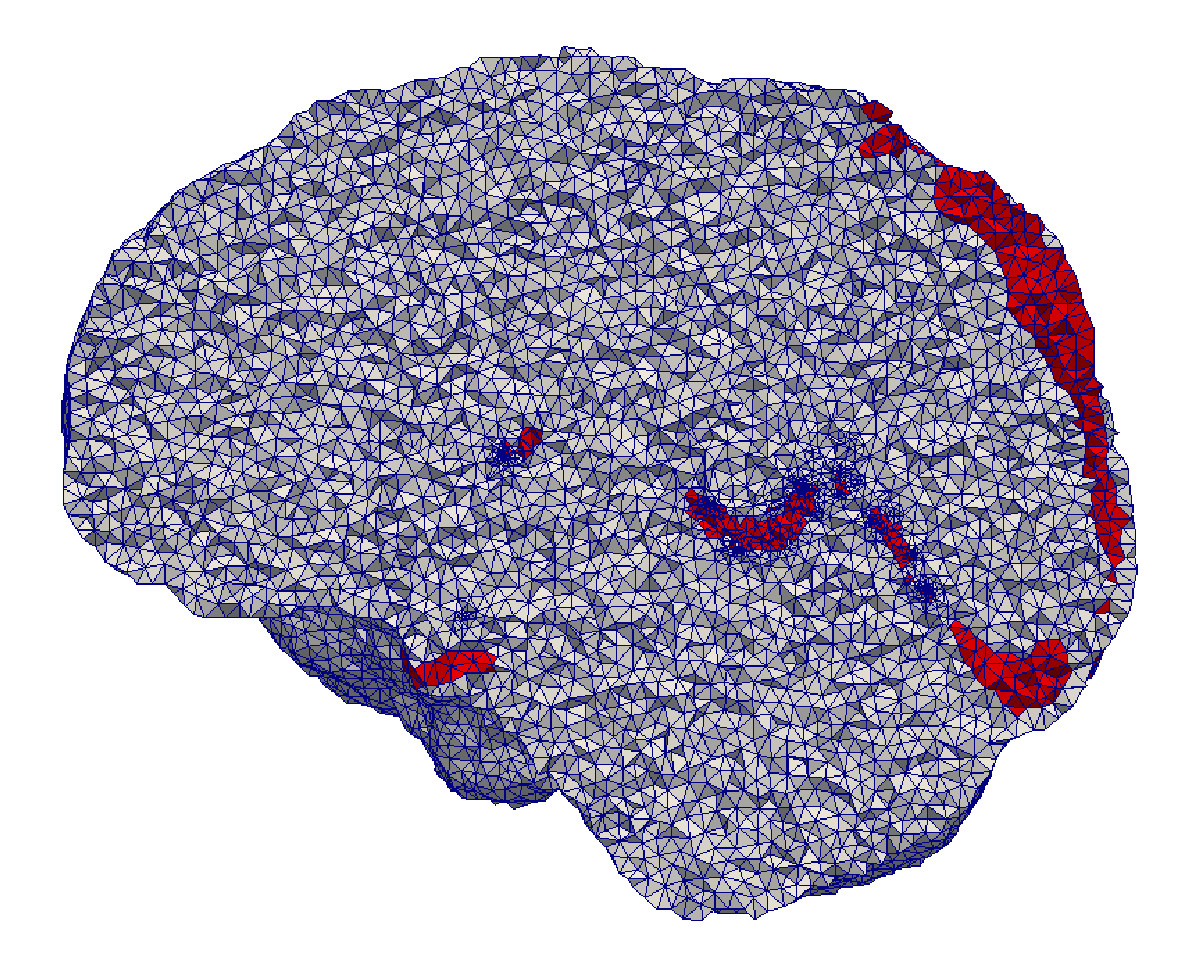

The mesh fidelity is qualitatively evaluated on AVM data (case 3). For this purpose, the AVM mesh is first extracted from the multi-material mesh and then superimposed on the AVM segmentation (Figure 22). The closer the mesh surface is to the boundary of the segmented AVM image, the higher the fidelity. The LD method achieves high fidelity because it completely resolves the vessels (it creates a voxelized mesh surface). Nevertheless, Figure 22e indicates a small shift in the output mesh in relation to the input image, most likely due to image resampling. CLEAVER resolves most of the vessel structures, but the generated mesh is noticeably shifted (Figure 22d). CBC3D achieves satisfactory fidelity. CBC3D’s mesh topological checks are turned off to avoid further red-green subdivisions, keeping the element count low.

Refer to caption

(a) AVM image

(b) CBC3D

(c) CGAL

(d) CLEAVER

(e) LD

(f) PODM

Figure 22: Qualitative evaluation on the fidelity of AVM mesh. Figures LABEL:sub@AVMFidelityOne- LABEL:sub@AVMFidelityFive depict the AVM mesh (red) superimposed on the AVM segmentation (blue). The closer the mesh surface is to the boundary of the segmented material, the higher the fidelity.